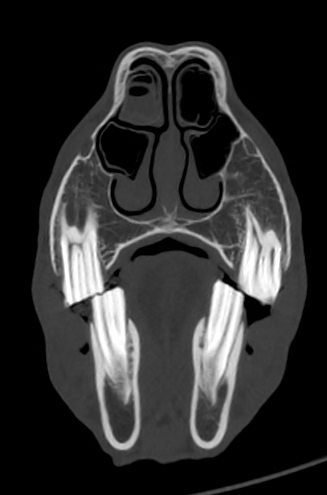

Mit dieser Technologie sind in der bildgebenden Diagnostik am Pferd völlig neue Optionen möglich. Wir sind in der Lage, sowohl am stehenden als auch am narkotisierten Pferd Aufnahmen mit bisher unvorstellbarer Detailschärfe dreidimensional anzufertigen. Das CT erfasst mehrere Querschnittsbilder, woraus im Nachhinein ein 3D-Bild erstellt wird. Dadurch erhalten wir Kenntnisse über die Größe, Lage und Struktur einer Veränderung und haben die Möglichkeit einer präzisen Diagnostik und eine effektive Therapie festzulegen.

Das CT wird jedoch nicht nur in Vollnarkose genutzt, sondern kann auch am stehenden Pferd angewendet werden, da für eine Distanz von 18cm gerade mal drei Sekunden benötigt werden. Dadurch sind Artefakt die durch Bewegung des Pferdes entstehen, kaum noch ein auftretendes Problem.  Für die Untersuchung im Stehen kann die Gantry in zwei Ebenen verstellt werden (siehe Video), was eine Behandlung ohne Vollnarkose vereinfacht und angenehmer für das Pferd macht.  Am stehenden Pferd haben wir die Möglichkeit den Kopf, die ersten Wirbel der Halswirbelsäule und die unteren Gliedmaßen bis Carpus/Tarsus zu untersuchen. In Vollnarkose können zusätzlich (je nach Größe des Pferdes) der Ellenbogen, die ersten Brustwirbel, das Knie, Becken und teilweise sogar Abdomen untersucht werden. Durch eine Kranverbindung von OP und Behandlungsraum und der kurzen Untersuchungsdauer im CT,  können wir vor, nach oder sogar während einer OP das CT als bildgebendes Verfahren nutzen, ohne dem Patienten einer langen Narkosedauer auszusetzen.